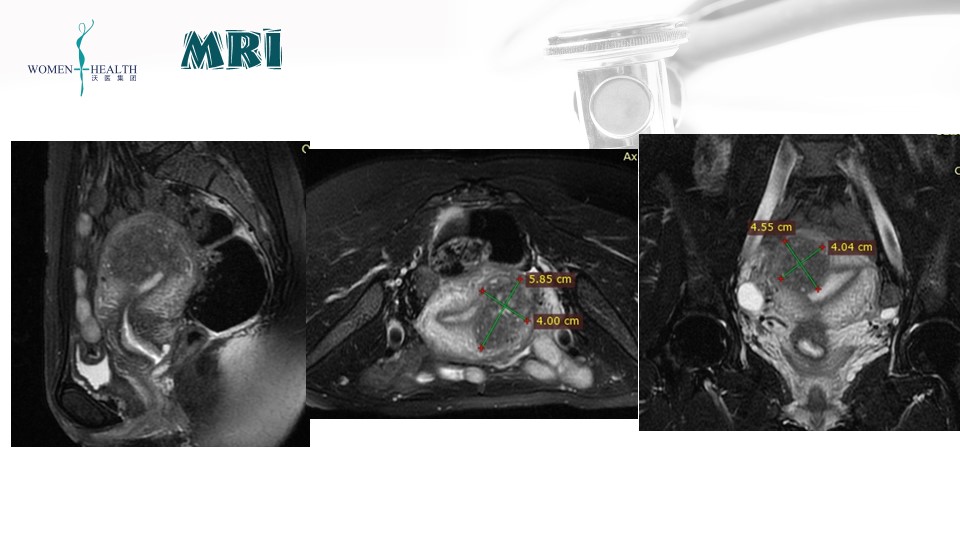

阴道超声(2023-2-11):子宫前壁欠均,局部39*29mm。MRI提示宫底靠近前壁腺肌症病灶59*40*46mm。